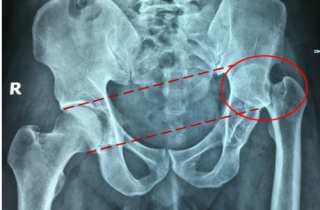

Bệnh nhân được bác sĩ tại TP HCM phẫu thuật thay khớp háng toàn phần để có dáng đi bình thường.

Chia sẻ